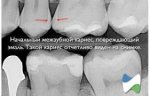

image.png

>>1636864

а как бяка может долго там сидеть, если ты ежедневно очищаешь? Другое дело капюшон у зуба, куда еда забивается - оно там просто гниет, но это не кариес. Но гнилостный тухлый запах - обычно проблема с зубом (пульпит, кариес, болезнь десны). Как вариант еще камень может быть.

Еще вариант - киста, она тоже может давать боль между зубами, хотя может казаться, что порезал десну.

Тебе снимок КТ делали или обычный черно-белый? На КТ и кариес виден (но могут быть погрешности) и киста